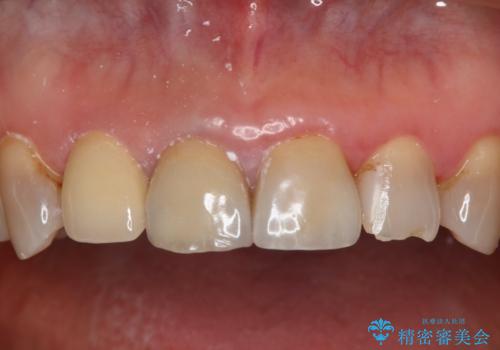

- 右上大臼歯の再治療を希望され来院された患者様です。

切削量と形状を考慮し、インレーでの治療を計画しました。

患者様がゴールドを希望されたのでゴールドインレーを選択しました。